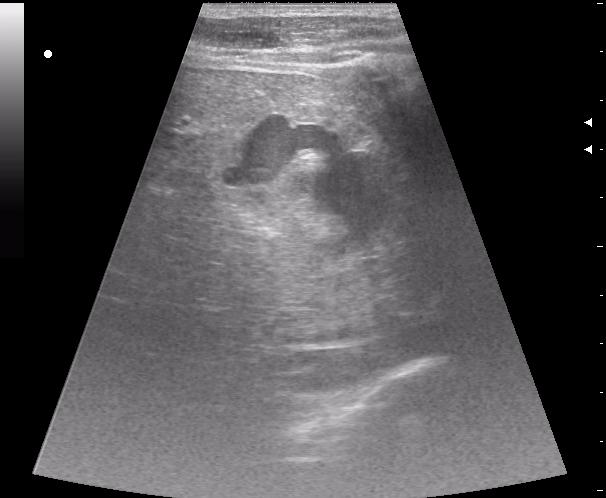

12-перстная, несмотря на свой пугающий вид, целая